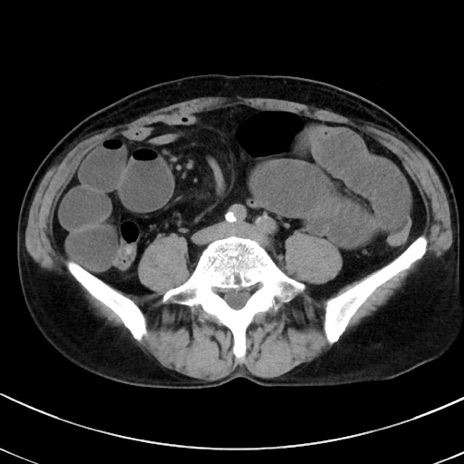

症例38(横断像)

【症例】70歳代 男性

【主訴】腹痛・嘔吐

【現病歴】昨晩より、嘔吐・腹痛あり。今朝になっても嘔吐あり。来院。

【既往歴】心臓バイパス手術、開腹胆摘、腸閉塞

【身体所見】BP 107/71mmHg、HR 116/min、腹部:平坦、軟、下腹部に軽度圧痛あり。反跳痛なし。

【データ】WBC 15100、CRP 0.32